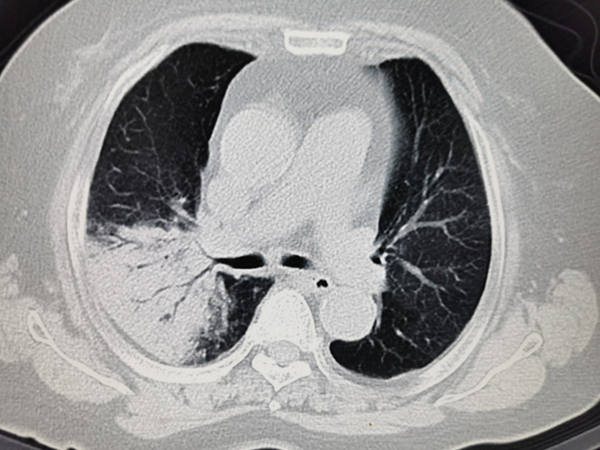

但对于咳嗽迁延超过8周的慢性咳嗽患者,则需要注意可能存在肺部疾病或其它系统疾病,这时就需要进行胸部影像学检查。

● 若胸部影像检查异常者,需进一步明确引起咳嗽的原因是否为肺炎、肺癌、肺结核、支气管扩张、慢性阻塞性肺疾病等其他肺部疾病。

● 若胸部影像检查正常患者,则需要进一步检查以明确病因,要考虑到是否存在其它系统疾病导致咳嗽的发生。